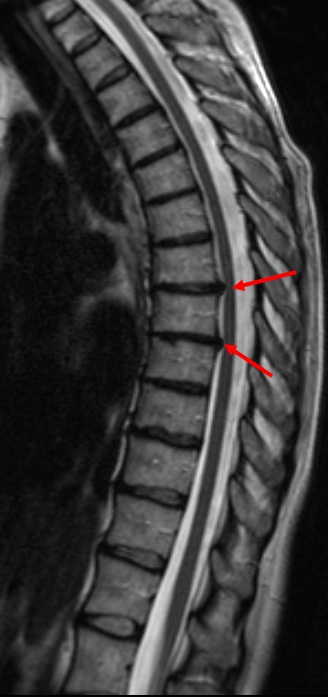

Как выглядит грыжа на МРТ снимке?

Наиболее часто диагностируются на МРТ грыжи поясничного отдела позвоночника, поскольку на область поясницы анатомически приходится наибольшая степень давления. В зависимости от стадии развития грыжи на МРТ сканах можно увидеть состояние:

- протрузии межпозвонкового диска (в виде трещин фиброзного кольца);

- пролапса или выхода внутреннего ядра за пределы диска, что сопровождается явлением воспаления и отека нервных корешков, их сдавлением

- секвестрированной грыжи – фрагментации ядра, смещения фрагментов в сторону спинно-мозгового канала.